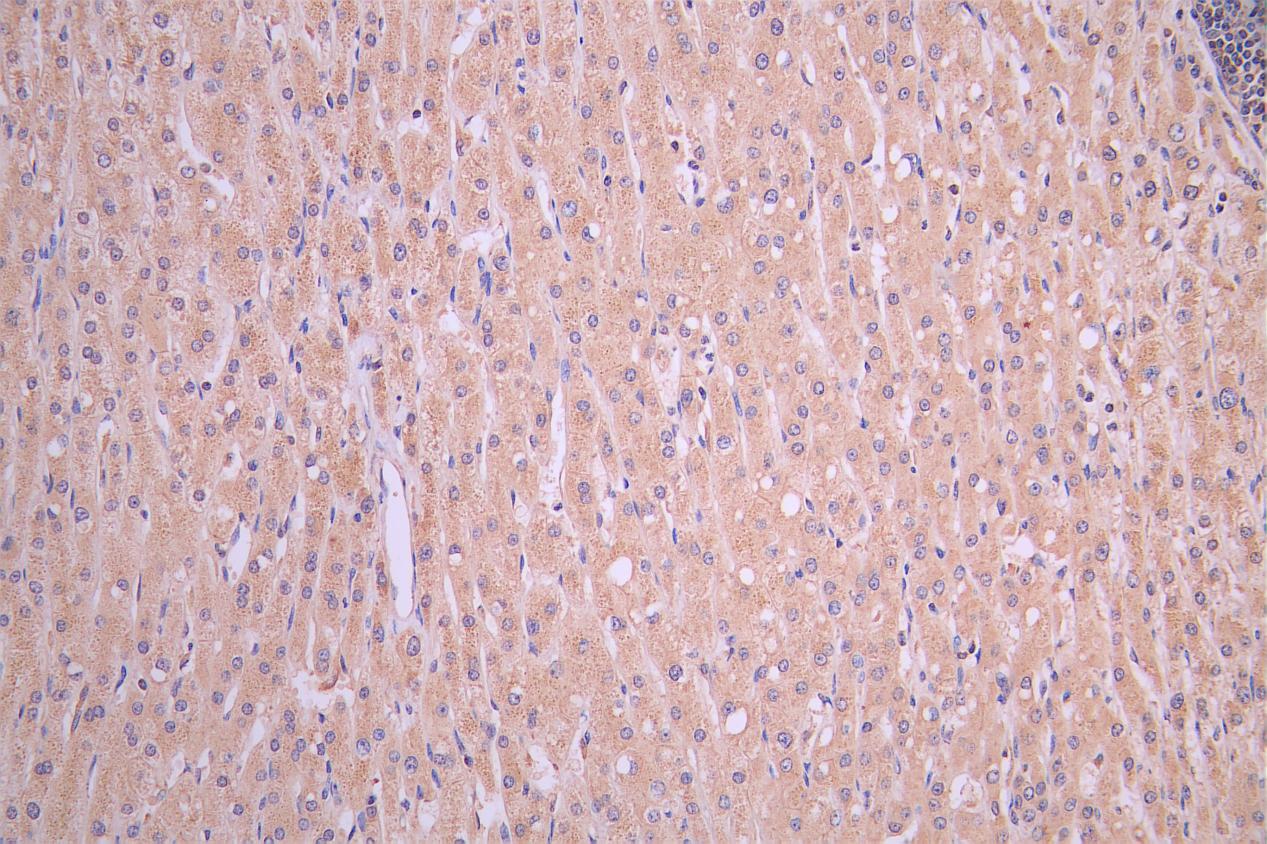

IHC image of CSB-PA009706LA01HU diluted at 1:50 and staining in paraffin-embedded human liver cancer performed on a Leica BondTM system. After dewaxing and hydration, antigen retrieval was mediated by high pressure in a citrate buffer (pH 6.0). Section was blocked with 10% normal goat serum 30min at RT. Then primary antibody (1% BSA) was incubated at 4°C overnight. The primary is detected by a Goat anti-rabbit polymer IgG labeled by HRP and visualized using 0.05% DAB.